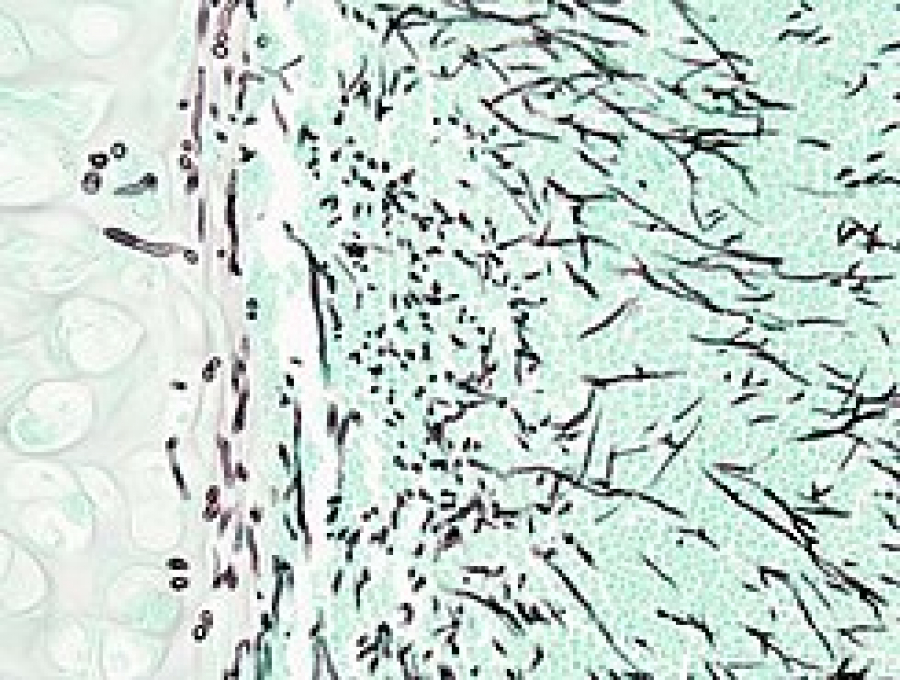

El tipo más grave es la aspergilosis invasiva, infección que se esparce por el cuerpo afectando órganos clave como el cerebro, riñones o el corazón. La aspergilosis pulmonar invasiva afecta a enfermos con sistemas inmunitarios débiles por estar sometidos a tratamientos de quimioterapia para luchar contra un cáncer, haber sufrido un trasplante de médula ósea o estar afectado por una enfermedad del sistema inmunitario.

Para diagnosticar la aspergilosis se tienen que realizar varias pruebas y análisis porque la observación de los síntomas no es suficiente, ya que puede llevar a confusión con otro tipo de enfermedades similares, agregó la Dra. Mónica Martínez Revelles.

Pruebas de diagnóstico por imágenes. Una radiografía de tórax o una tomografía computarizada ayudan a identificar la presencia del hongo aspergillus. Análisis de sangre y de varios tejidos, son necesarios estos análisis para confirmar la enfermedad.

Una vez identificado el nivel de gravedad de la enfermedad se da el tratamiento. En algunos casos leves no es necesario hacer nada porque la infección desaparece. Es normal administrarle al enfermo medicamentos antifúngicos y corticoesteroides. Si la infección se ha agravado y hay hemorragia pulmonar se puede llegar a requerir una intervención quirúrgica.